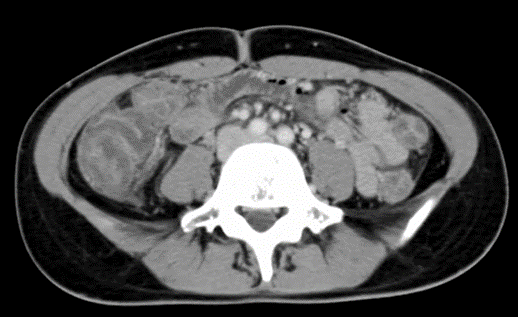

27歳女性。下腹部全体の痛みと頻回の下痢を主訴に来院。妊娠なし。造影CT施行。

所見:上行結腸に浮腫所見あり。

粘膜と外膜は造影効果が見られ、粘膜下層は浮腫状に肥厚して低吸収3層構造になっている。

右側結腸優位の著明な壁肥厚。病原性O-157であった症例。